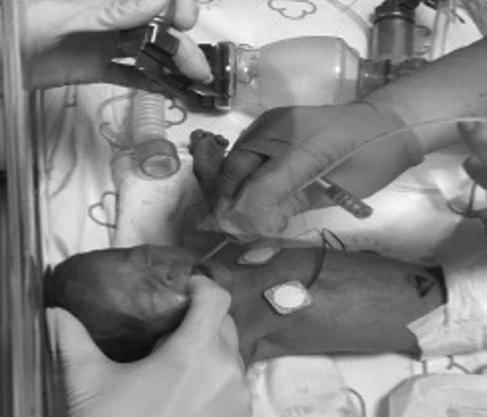

O primeiro reanimador continua a ventilação, enquanto o segundo inicia as compressões torácicas: compressão sobre o terço inferior do esterno, imediatamente abaixo da linha intermamilar, evitando o apêndice xifoide.

■ Técnica dos polegares ou abraço (Figura 2.4): a compressão é feita abraçando o tórax do RN com as duas mãos e usando os polegares para deprimir

20 Neonatologia – Procedimentos Técnicos

o tórax. Esta técnica é considerada mais eficaz, se exequível, tendo em conta o tamanho do RN e das mãos do reanimador;

■ Técnica dos dois dedos (Figura 2.5): as pontas dos dedos médio e indicador ou anelar da mesma mão (a direita, em pessoas dextras) são utilizadas para comprimir o esterno, na perpendicular ao tronco do RN.

Figura 2.4 – Técnica dos polegares ou abraço. Figura 2.5 – Técnica dos dois dedos.